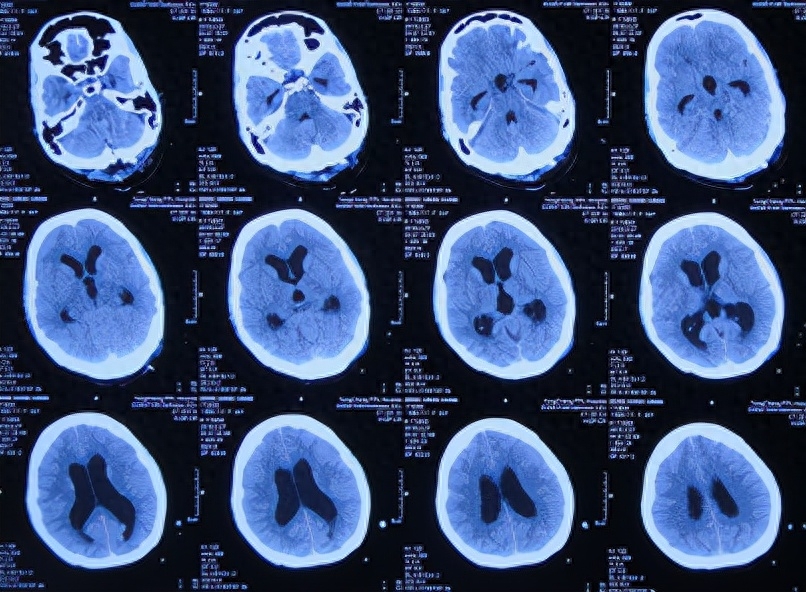

一、李小勇脑脊液科入院前病史

患者2019年2月初,因数次出现发作性黑蒙,2019年2月10日就诊于当地的河南省永城市某医院,查头颅CT未见明显异常(图-1);次日再查头颅核磁、颈椎核磁(图-2、图-3)后发现小脑扁桃体下疝畸形合并脊髓空洞。

图-1:2019年2月10日头颅CT